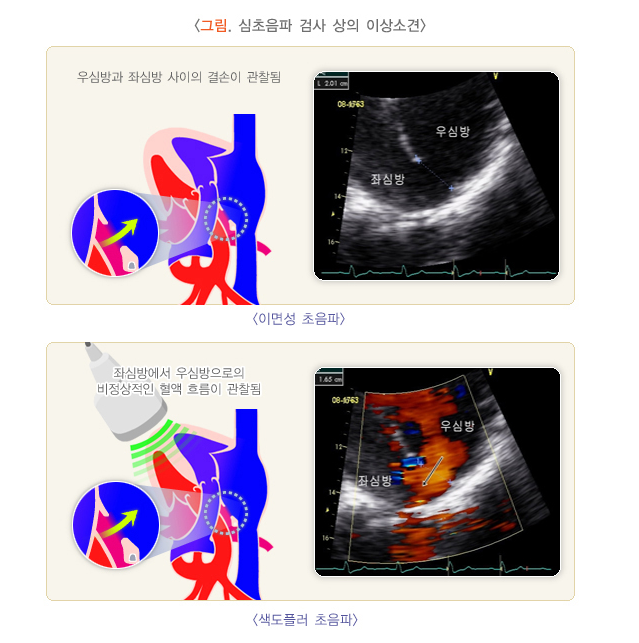

5. 심장 초음파 검사 (Echocardiography)

- 심장 구조 평가: 심장 초음파는 심장의 구조와 기능을 평가하는 검사로, 심실성 부정맥의 원인(예: 심장질환, 심장벽 비대, 심장 내 혈전 등)을 파악하는 데 도움을 줍니다. 심장이 제대로 기능하지 않거나 심장벽에 이상이 있는 경우, 부정맥이 유발될 수 있습니다.

- 심근경색, 심부전, 심장 재구성 등의 원인에 따른 심장의 기능과 구조적 이상을 확인할 수 있습니다.